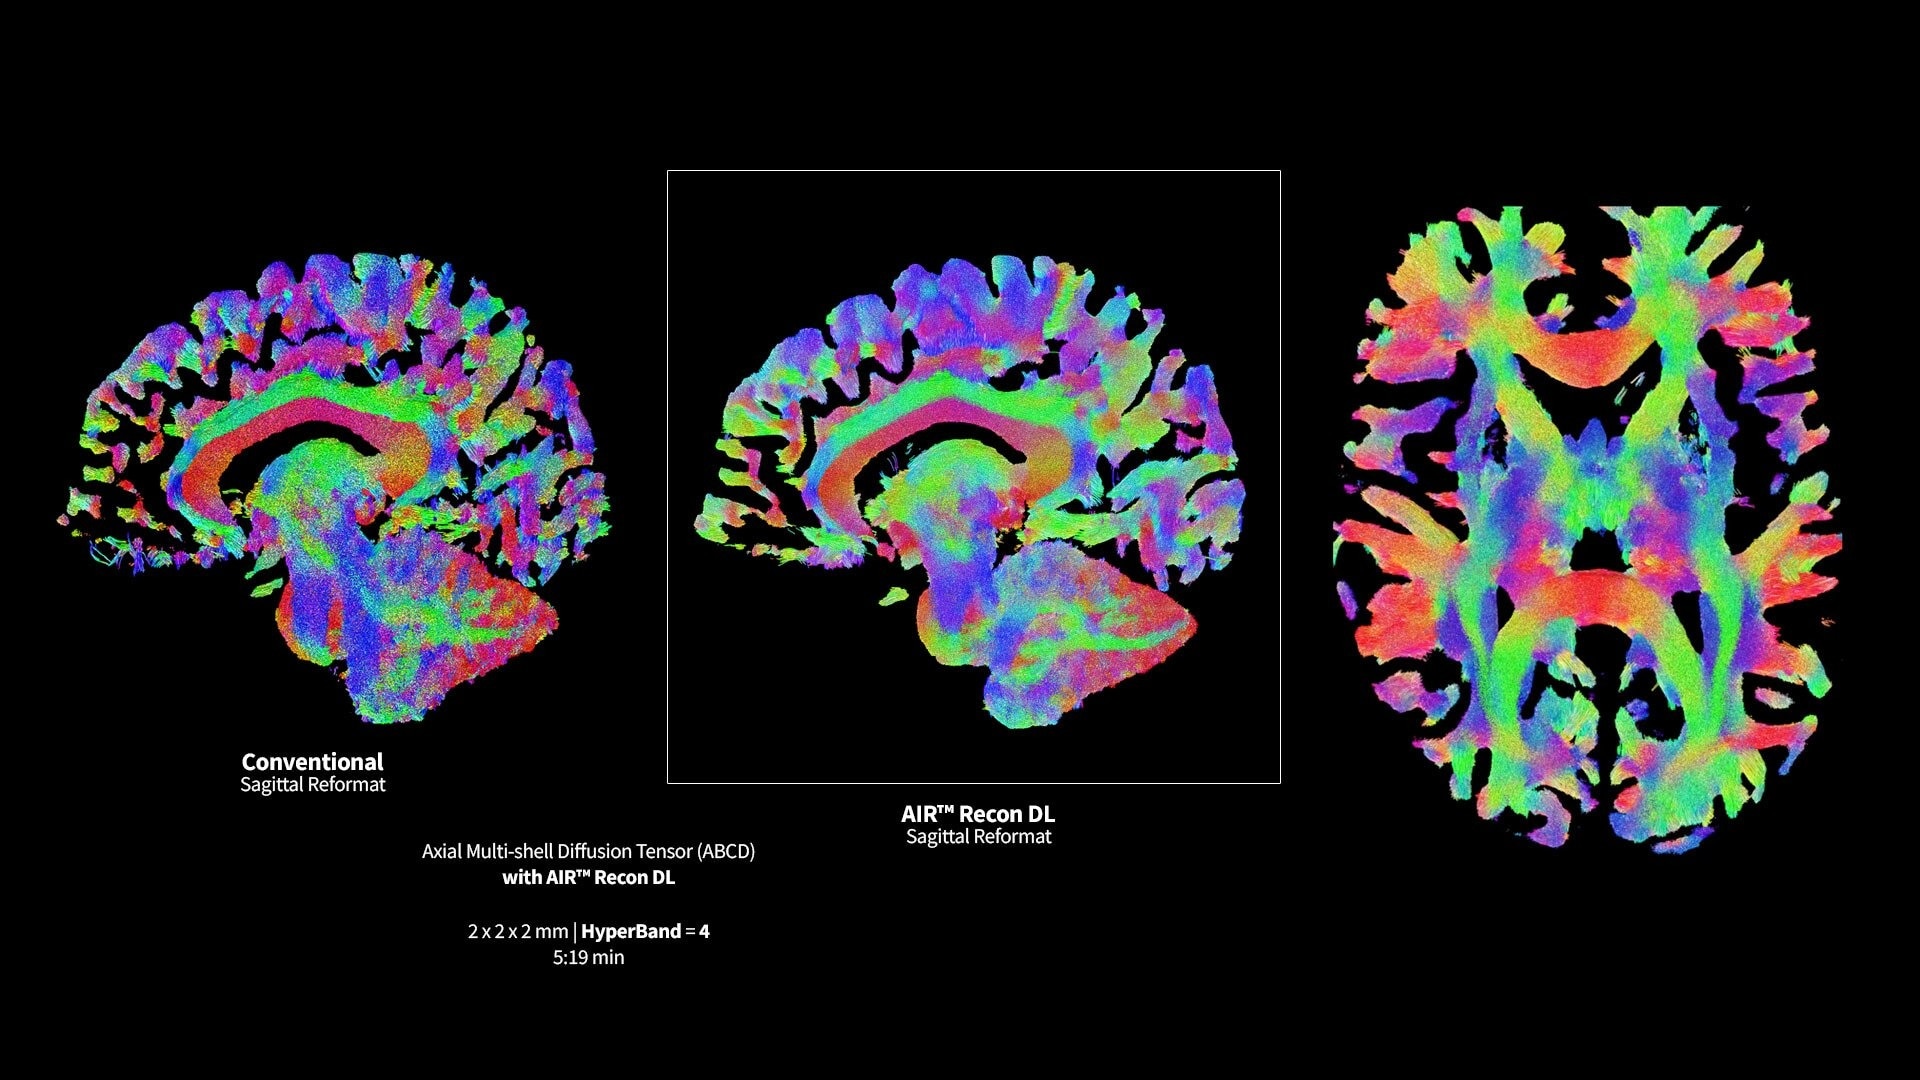

<p>Advanced DWI</p>

Read case study ico-caret-right

GE HealthCare’s AIR x deep-learning prescription tool for automated slice placement ensures consistent image setup across follow-up exams and patients. Effortless DL reconstruction with AIR Recon DL reduces noise and scan time up to 50%, while improving SNR.